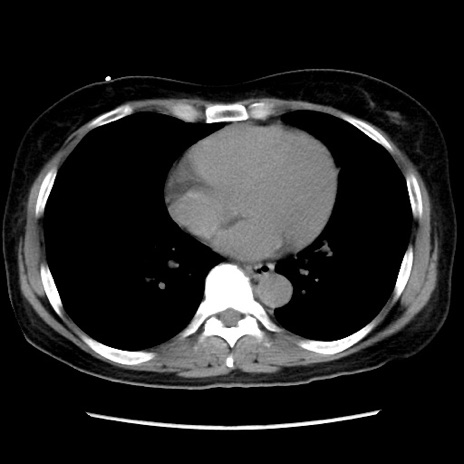

症例10(横断像)

【症例】 50歳代女性

【主訴】 腹痛

【現病歴】前日生レバーを食べた。今朝に排便あり。 昼前に突然発症の腹痛を生じ、当院救急外来を受診した。

【既往歴】 子宮筋腫にてで子宮全摘後

【身体所見】 意識清明、腹部:平坦、軟、下腹部やや左を中心に圧痛・反跳痛あり、筋性防御あり

【データ】WBC 7800、CRP 0.07